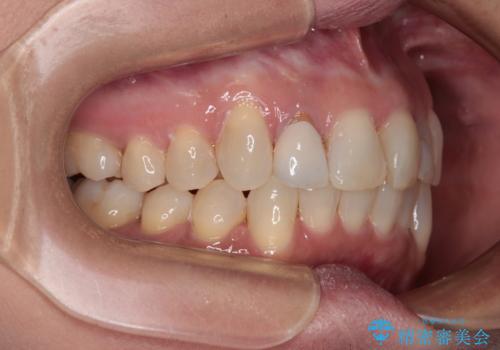

前歯のデコボコとむし歯治療の跡 インビザライン矯正とオールセラミッククラウン治療

- 前歯のセラミッククラウンの縁が見えることが気になってから、デコボコも気になるようになってきたとのことで来院された患者様です。

デコボコの程度は中等度であったため、インビザライン・モデレートパッケージにて歯列を整えることとしました。

セラミッククラウンの装着されていた前歯と、大きな修復治療の跡がある反対側の歯は、矯正治療後に補綴治療を行うこととしました。